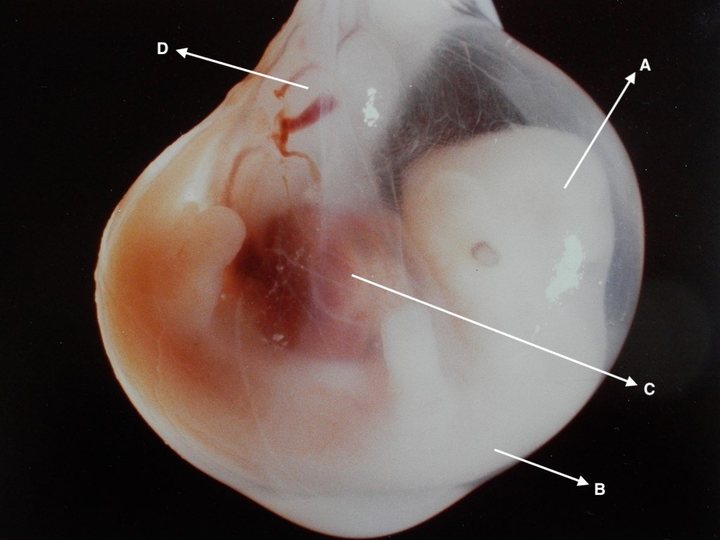

Which of the following structures marked in the below image gives rise to the heart in an adult?

A young patient presented with hypoparathyroidism, absent thymus and tetany. Which of the following marked areas in the picture is defective in this condition?